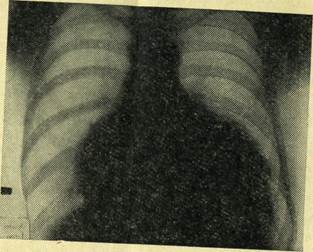

Рис.10 Рентгенограмма: коллапс правого легкого при открытом пневмотораксе.

Рис.11 Механизм развития клапанного (напряженного) пневмоторакса.